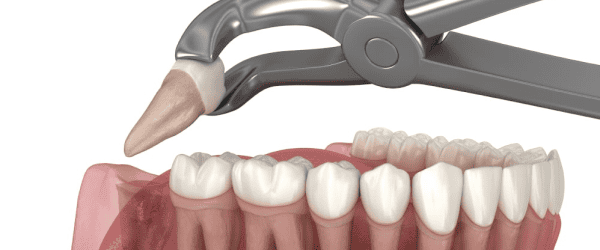

Our oral surgeon gently removes the wisdom teeth using precise techniques, minimizing trauma to surrounding tissue for a smooth recovery.

We take measures to ensure the extraction process is as painless as possible, using local anesthesia to numb the area. Some discomfort following the procedure is normal but can be managed with prescribed pain relief.